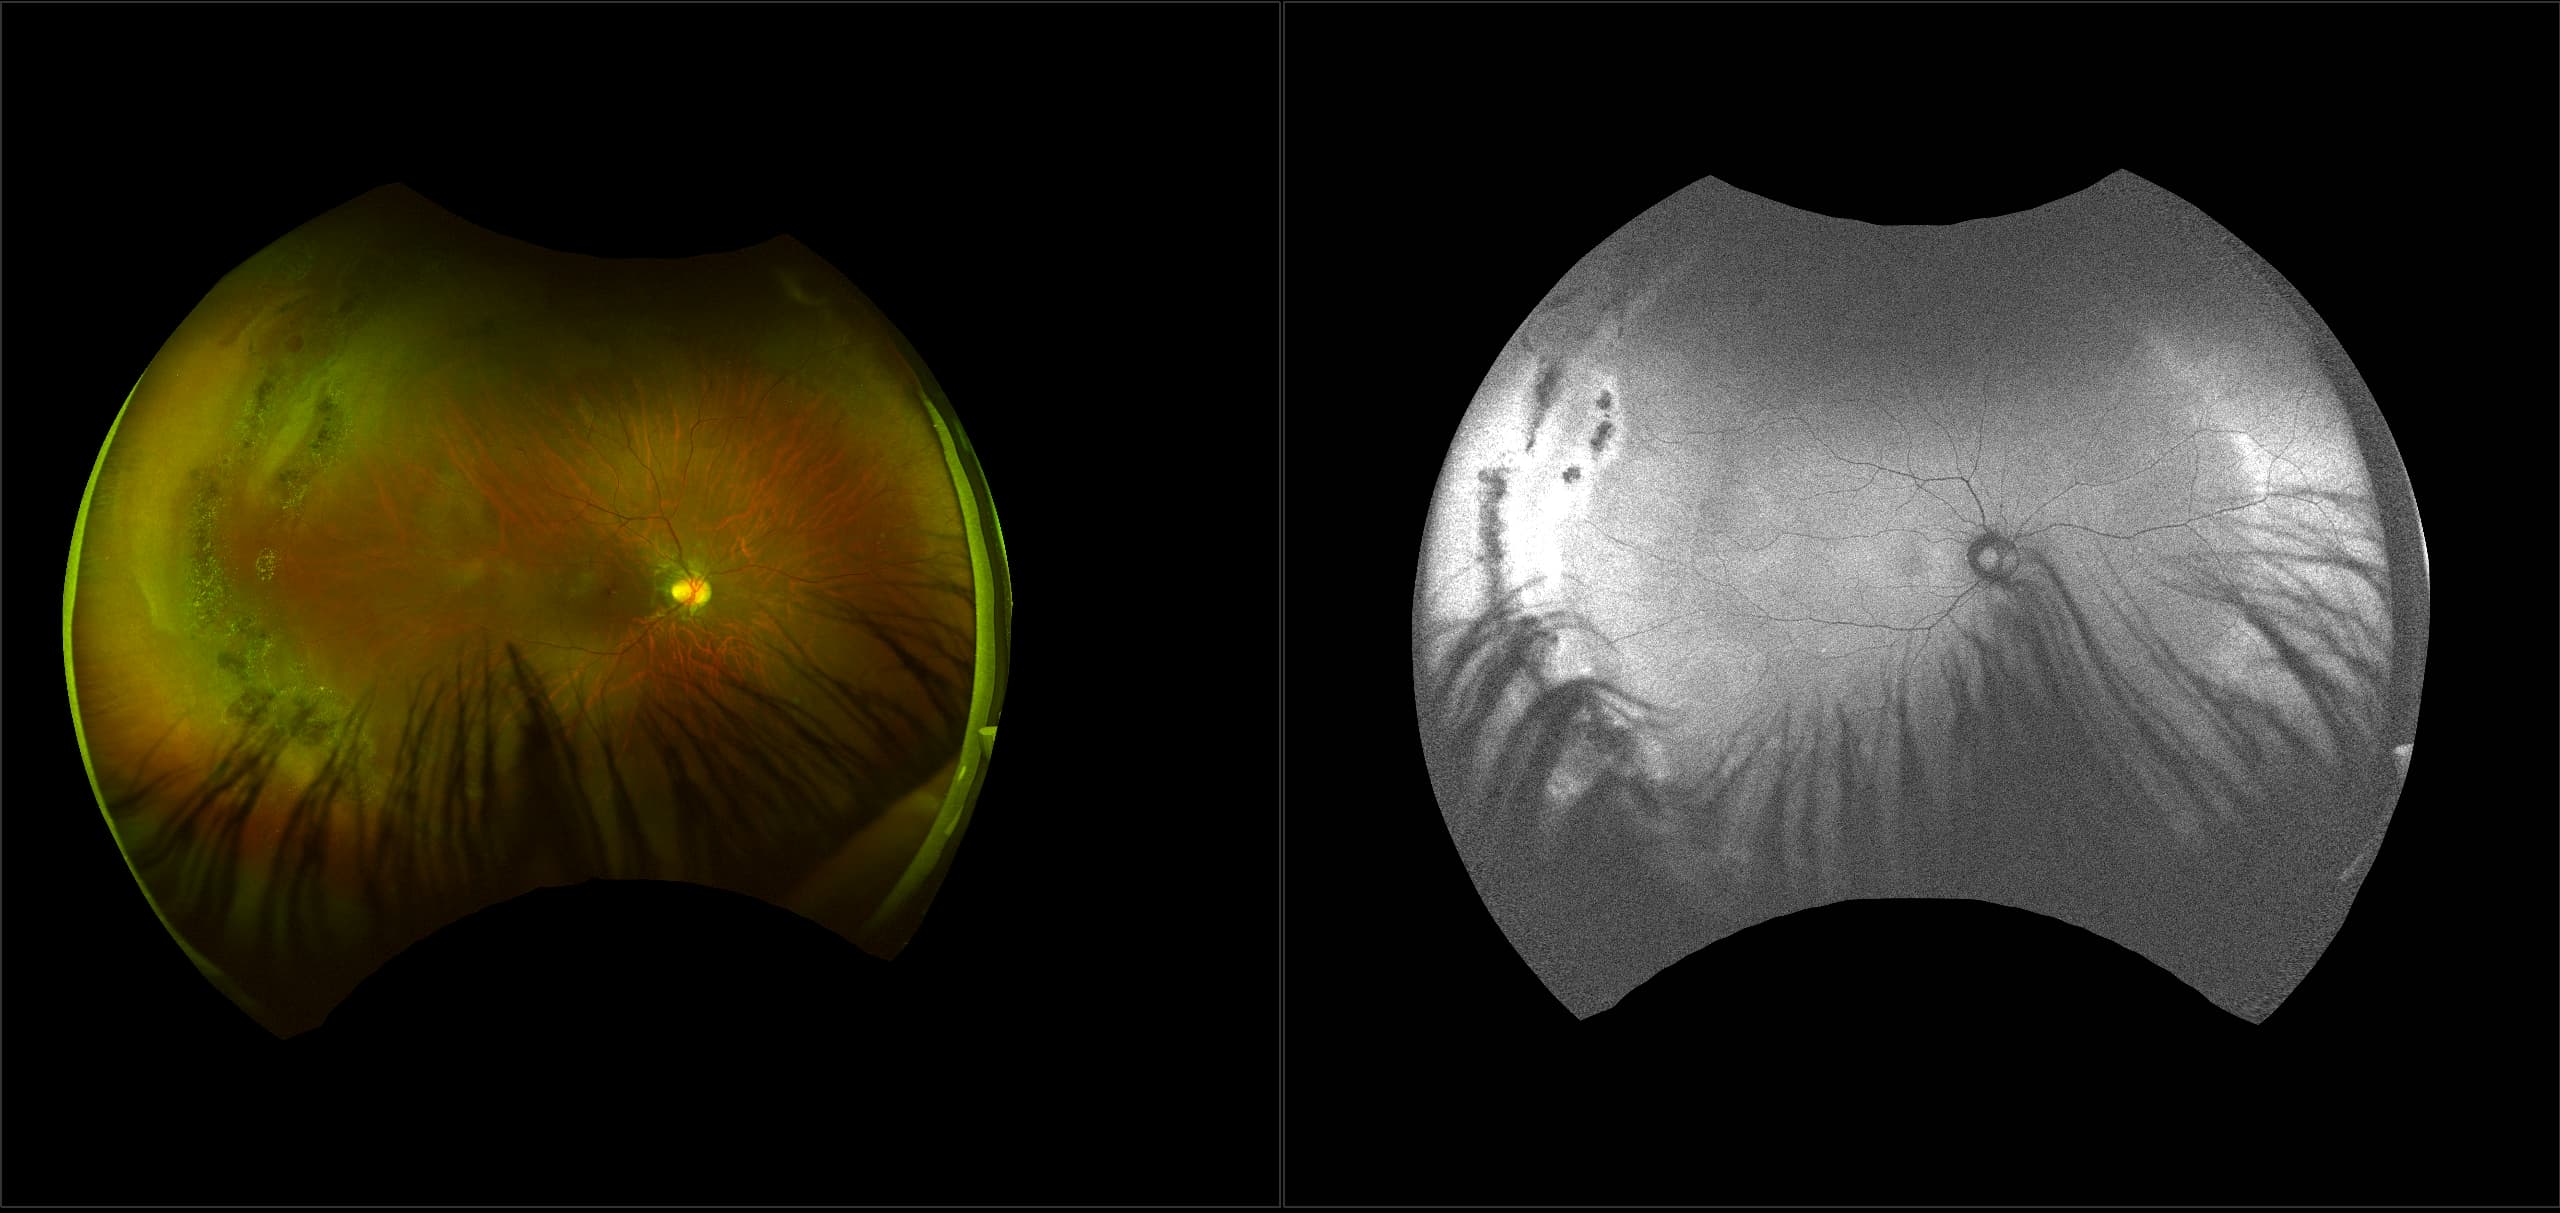

Monaco - Pigment Epithelial Detachment, RG, OCT

In some eyes, there may be small areas of the retina that are torn, or holes may develop. These areas, called retinal breaks, can lead to retinal detachment. Retinal breaks are often caused by traction from the vitreous, the gel that fills the back of the eye. Traction can occur as the vitreous pulls away from the retina, which occurs with age, trauma, surgery, inflammation, and near-sightedness.